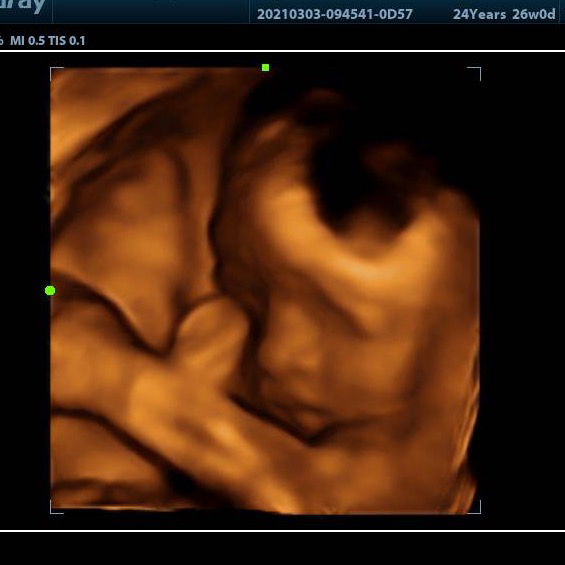

Muka merah bruntusan

Moms ini muka baby saya kenapa ya? Bruntusan merah gitu.. sabunnya udah saya ganti pake lactacyd baby, baru pake 3 hari belum sembuh2.. atau masih proses ya moms?